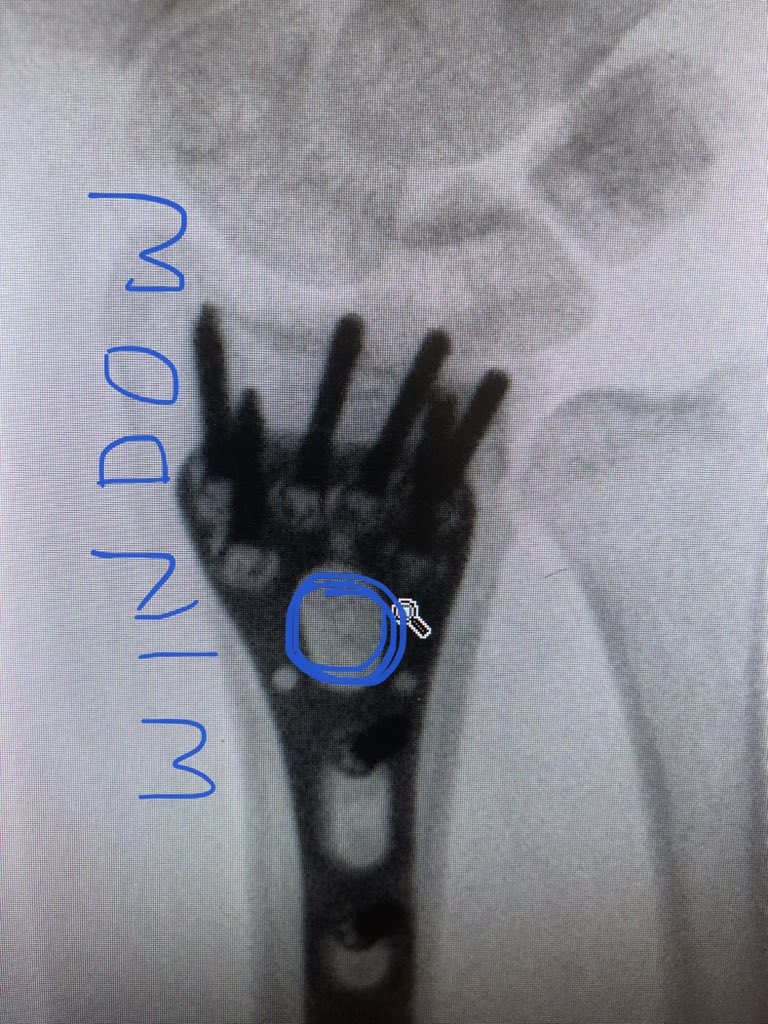

Point 2:

The dorsal metaphyseal comminution. The dorsal cortex fragment is ‘fallen in’ inside the osteoporotic metaphyseal void.

I addressed this after plating finished, made a 4.5 mm drill hole in the ‘window’ of the plate to push the fragment and fill in graft substitute.